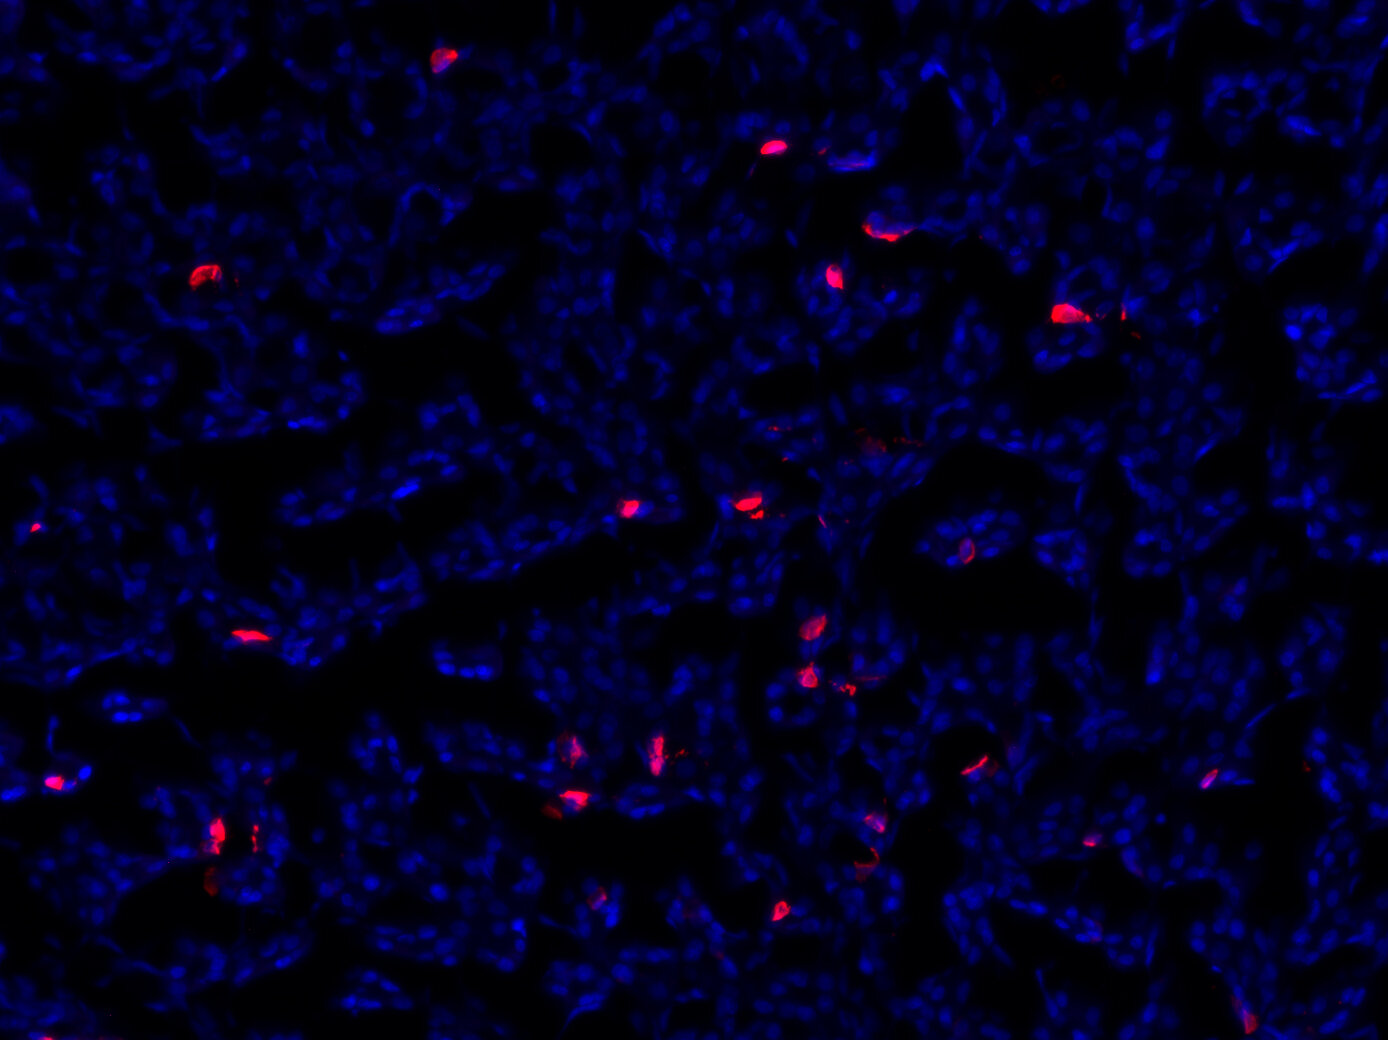

IHC: 1 : 500 gallery

IHC-P: 1 : 200 up to 1 : 1000 gallery

Ghrelin is produced predominantly by endocrine X/A-like cells of the stomach submucosa, from where it is secreted into the plasma (1). It is also present in other parts of the gastrointestinal tract, while substantially lower amounts derive from other tissues including the pancreas. In pancreatic islets, ghrelin producing epsilon cells are primarily found during gestational development (2,3). After birth, epsilon cell numbers gradually decline (2,3).